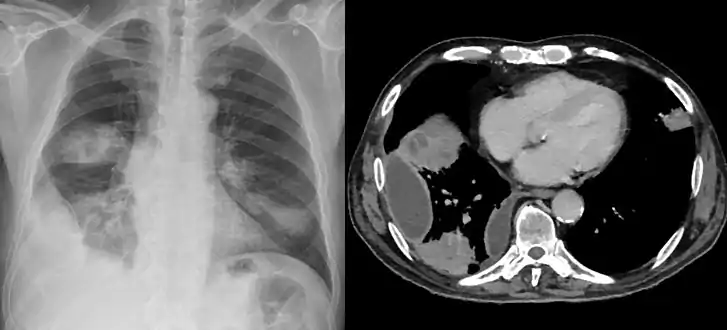

Lungs

Empyema

Empyema with abscess